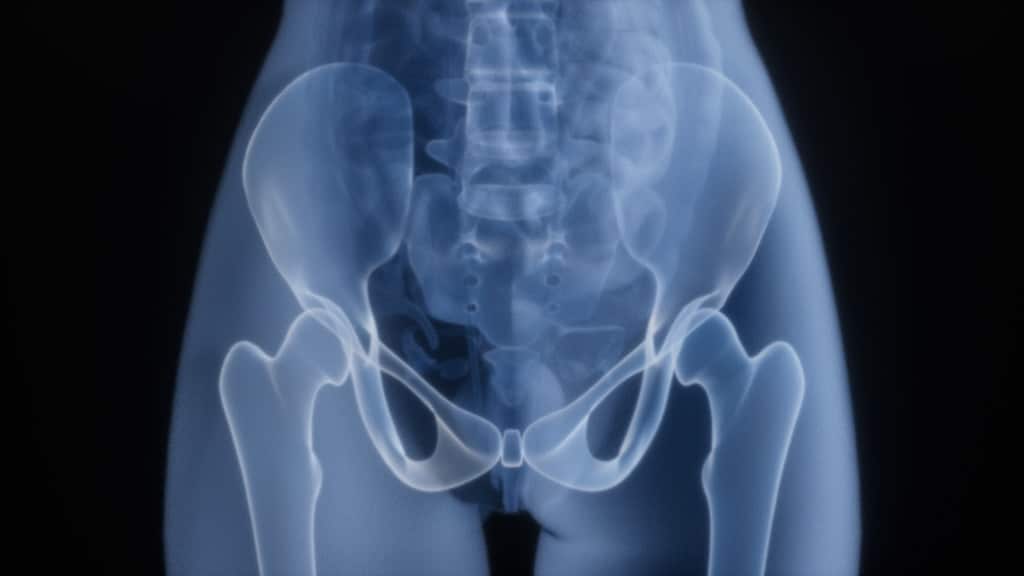

Staw biodrowy to jeden z największych i najbardziej obciążonych stawów w ludzkim organizmie. Jako połączenie kuliste przenosi on ciężar całego tułowia na kończyny dolne, umożliwiając nam lokomocję, utrzymanie pionowej postawy oraz wykonywanie złożonych ruchów w trzech płaszczyznach. Ze względu na ogromne siły, jakie oddziałują na panewkę i głowę kości udowej, struktura ta wymaga doskonałego zbalansowania siły mięśniowej oraz elastyczności tkanek miękkich.

Skuteczne działanie w obszarze ortopedii biodra wymaga precyzyjnego planowania. Podstawą jest RTG w odpowiednich projekcjach, jednak aby ocenić stan chrząstki i tkanek miękkich, niezbędny bywa rezonans magnetyczny (często z kontrastem podawanym dostawowo).